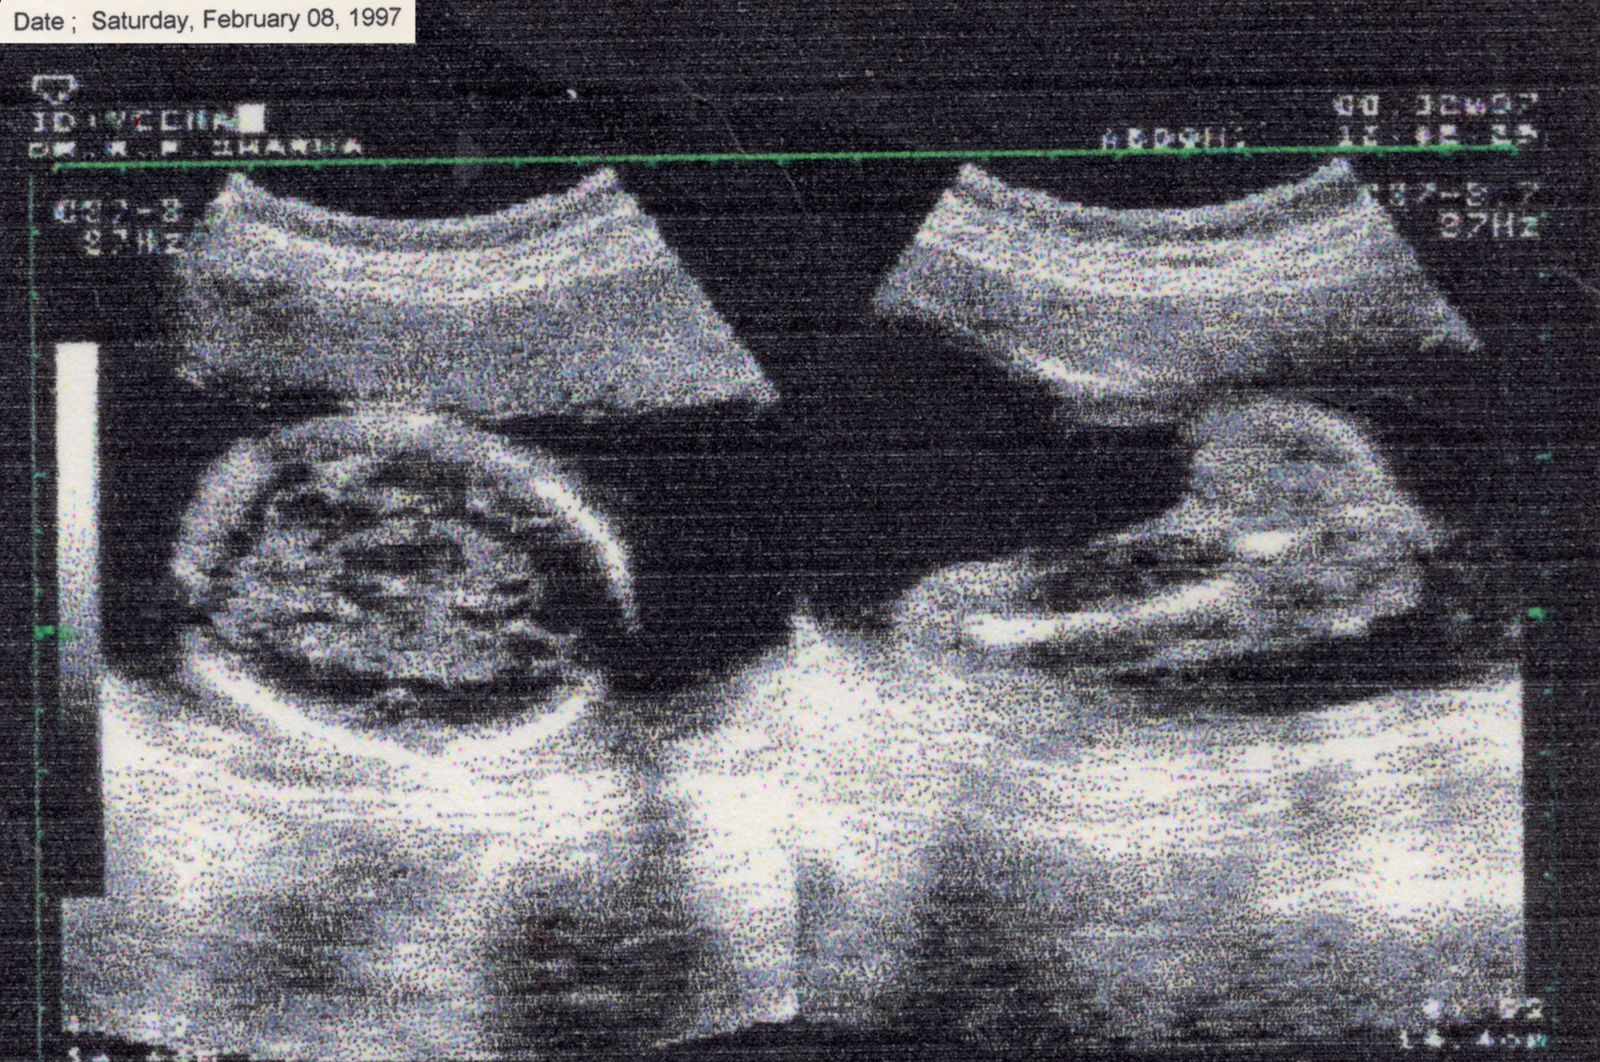

There Is No Other Home emerges from the space between chaos and understanding. My body often feels like it carries its own memory. My hands loose grip, I stumble more often, and I freeze at things others take for granted, like driving. I return to fragments of memory, my mother’s CT scan when she was carrying me and my twin sister, a childhood photograph, not as evidence of illness but as traces of fragility, endurance, and survival.